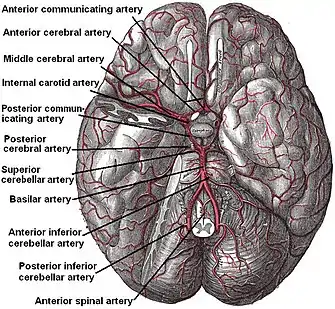

According to Koffler et al., lacunes are derived from an "occlusion of a single deep penetrating artery that arises directly from the constituents of the circle of Willis, cerebellar arteries, and basilar artery". Other lesions that are associated with lacunes appear in the "deep nuclei of the brain (37% putamen, 14% thalamus, and 10% caudate) as well as the pons (16%) or the posterior limb of the internal capsule (10%)". These lesions are less common within other brain regions such as the cerebellum, cerebral white matter and anterior limb of the internal capsule.[9]

The two proposed mechanisms are microatheroma and lipohyalinosis.[10] At the beginning, lipohyalinosis was thought to be the main small vessel pathology, but microatheroma now is thought to be the most common mechanism of arterial occlusion (or stenosis). Occasionally, atheroma in the parent artery blocks the orifice of the penetrating artery (luminal atheroma), or atheroma involves the origin of the penetrating artery (junctional atheroma). Alternatively, hypoperfusion is believed to be the mechanism when there is stenosis of the penetrating artery. When no evidence of small vessel disease is found on histologic examination, an embolic cause is assumed, either artery-to-artery embolism or cardioembolism. In one recent series, 25% of patients with clinical radiologically defined lacunes had a potential cardiac cause for their strokes.